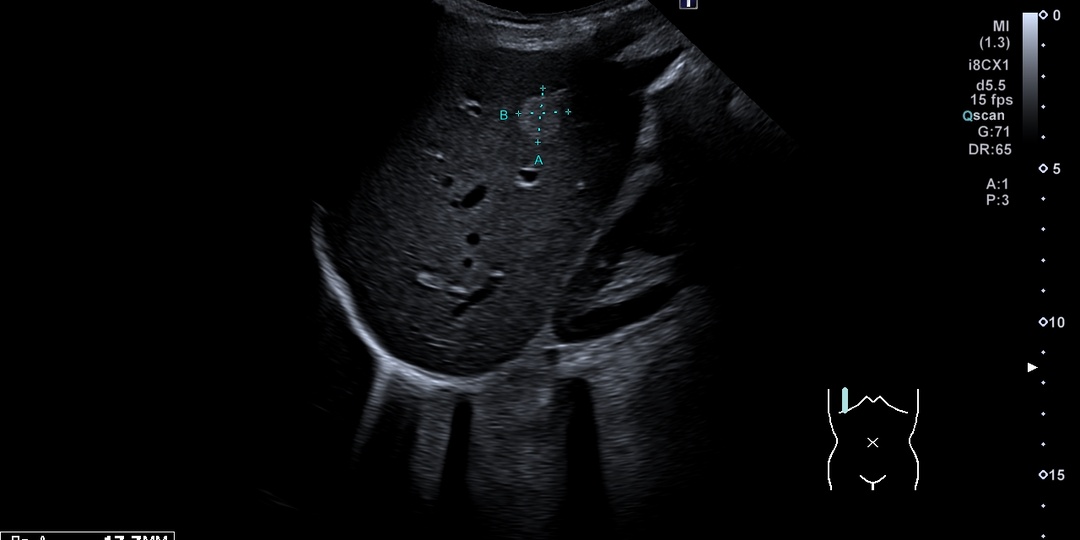

Гемангиома печени — это доброкачественная сосудистая опухоль, которая является наиболее распространенной некистозной опухолью печени. Происхождение гемангиомы печени у людей является сложным и многофакторным процессом, который включает генетические, эмбриологические и гормональные факторы. 1. Эмбриологическое происхождение и сосудистая мальформация

Гемангиомы печени считаются врожденными сосудистыми мальформациями, которые возникают в результате нарушений в развитии кровеносных сосудов во время эмбриогенеза [1]. Эти опухоли представляют собой мезенхимальные образования, состоящие из заполненных кровью сосудистых полостей различного размера, окруженных одним слоем плоских эндотелиальных клеток, поддерживаемых фиброзной соединительной тканью [2]. 2. Генетические факторы